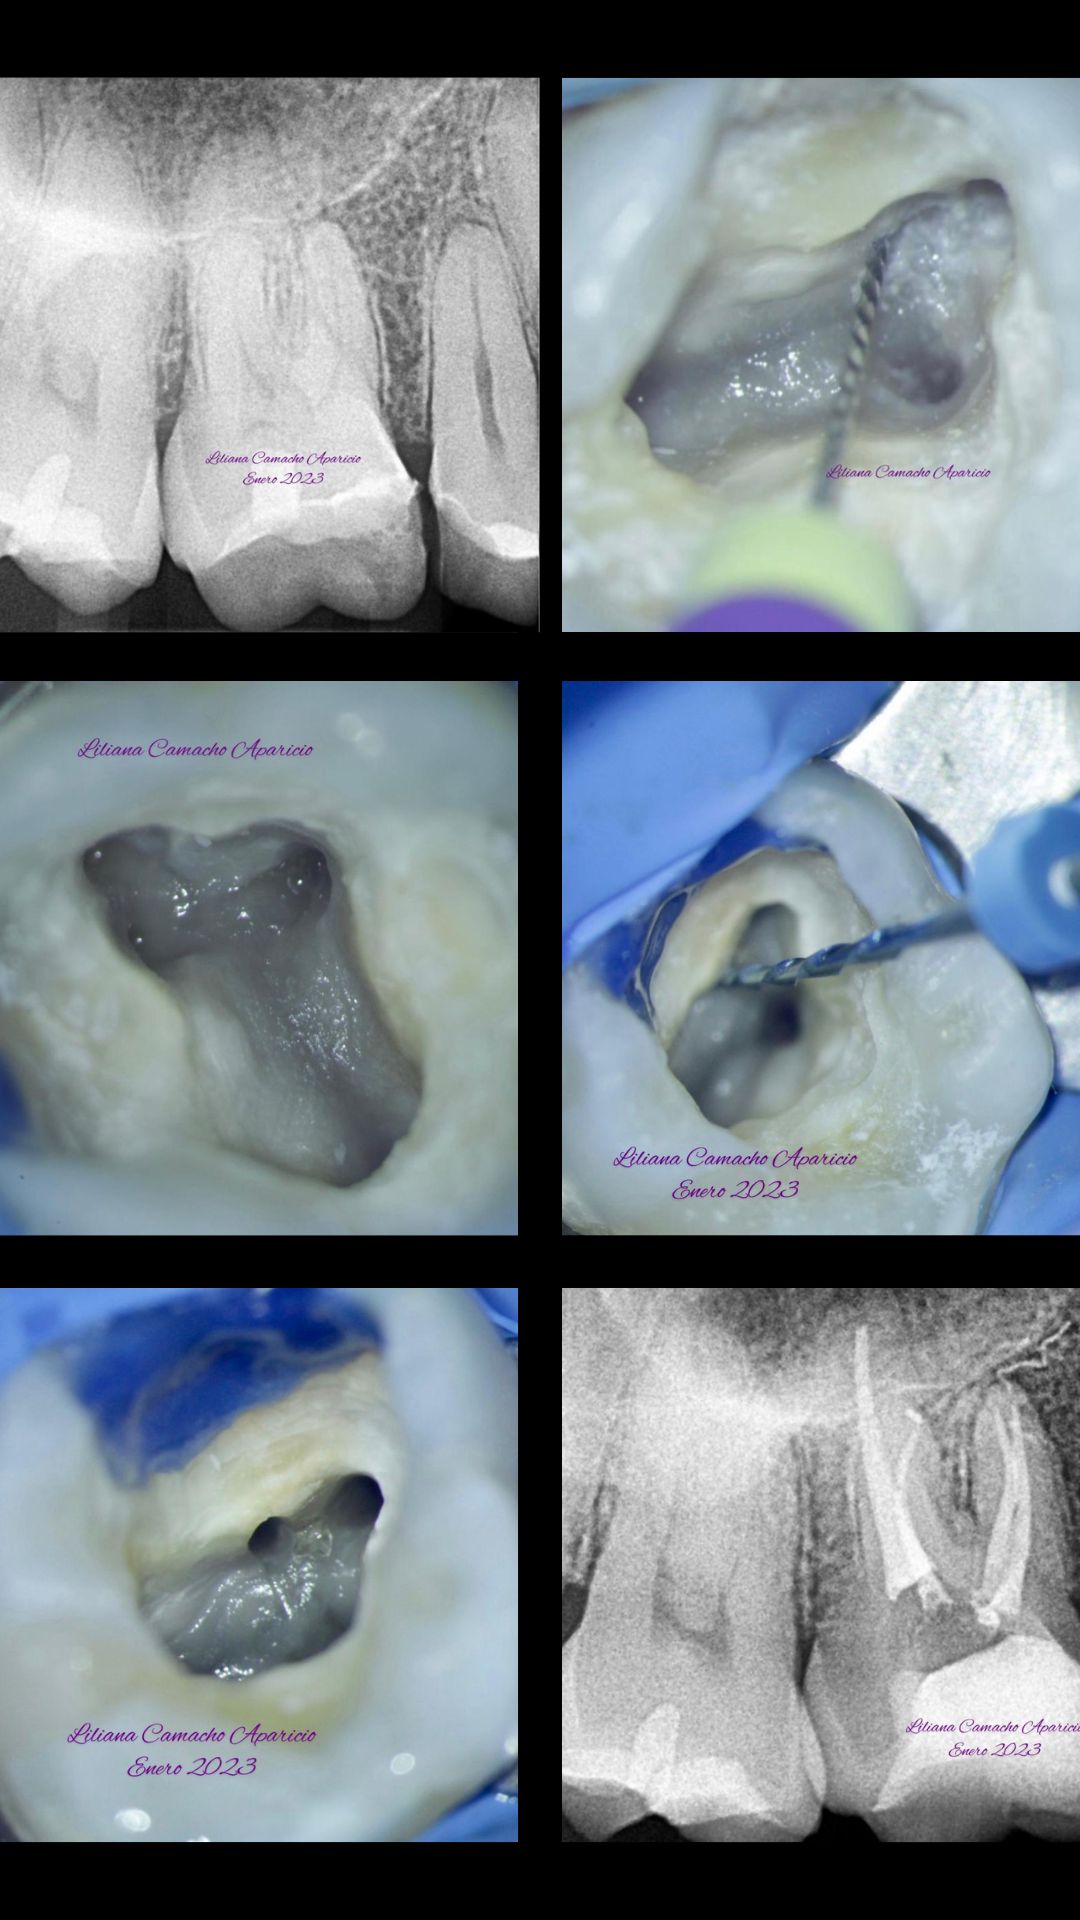

Hola soy Liliana A. Camacho Aparicio, soy Cirujano Dentista, Especialista en Endodoncia y Maestra en ciencias Odontológicas Clínicas con Mención Honorífica, tengo el gusto y el orgullo de haber realizado todos mis estudios profesionales y de posgrado en la Máxima Casa de Estudios, en la UNAM. Soy endodoncista certificada por el Consejo Mexicano de Endodoncia y recientemente cumplí 10 años de experiencia en práctica privada en mi consultorio, exclusivamente en el área de Endodoncia. Me encanta la práctica clínica y me gusta mucho actualizarme, hace 3 años comenzamos a utilizar microscopio en nuestros tratamientos y utilizamos la más alta tecnología en materiales, instrumentos y equipo. Recientemente cumplí también 10 años de ser docente en la UNAM, doy clases en el Posgrado de Endodoncia de la Facultad de Odontología de la UNAM, donde me apasiona también realizar investigación. Soy líder de opinión y conferencista de algunas casas comerciales de Endodoncia. Mi gran pasión es combinar la práctica clínica en mi consultorio, la docencia, la investigación y dar conferencias, todo esto me permite mantenerme actualizada y brindar la mejor atención que puedo a mis pacientes. Considero que la Endodoncia es una ciencia y un arte, requiere gran conocimiento, entrenamiento, paciencia y debe ser llevada a cabo de forma muy minuciosa y precisa, son tratamientos complejos que deben ser realizados por especialistas competentes y éticos. Por otro lado, comprendemos que las visitas odontológicas pueden generar tensión en los pacientes, conscientes de ello, hacemos nuestro mayor esfuerzo para que su tratamiento sea lo más agradable posible y sobre todo sin dolor. Mi equipo y yo los esperamos con mucho gusto en el consultorio si requieren algún tratamiento de conductos, será un placer atenderlos. Citas vía whats app, llamada al teléfono indicado en el perfil o directamente en la agenda de Doctoralia.

Endodoncia Microscópica Dra. Liliana A. Camacho Aparicio